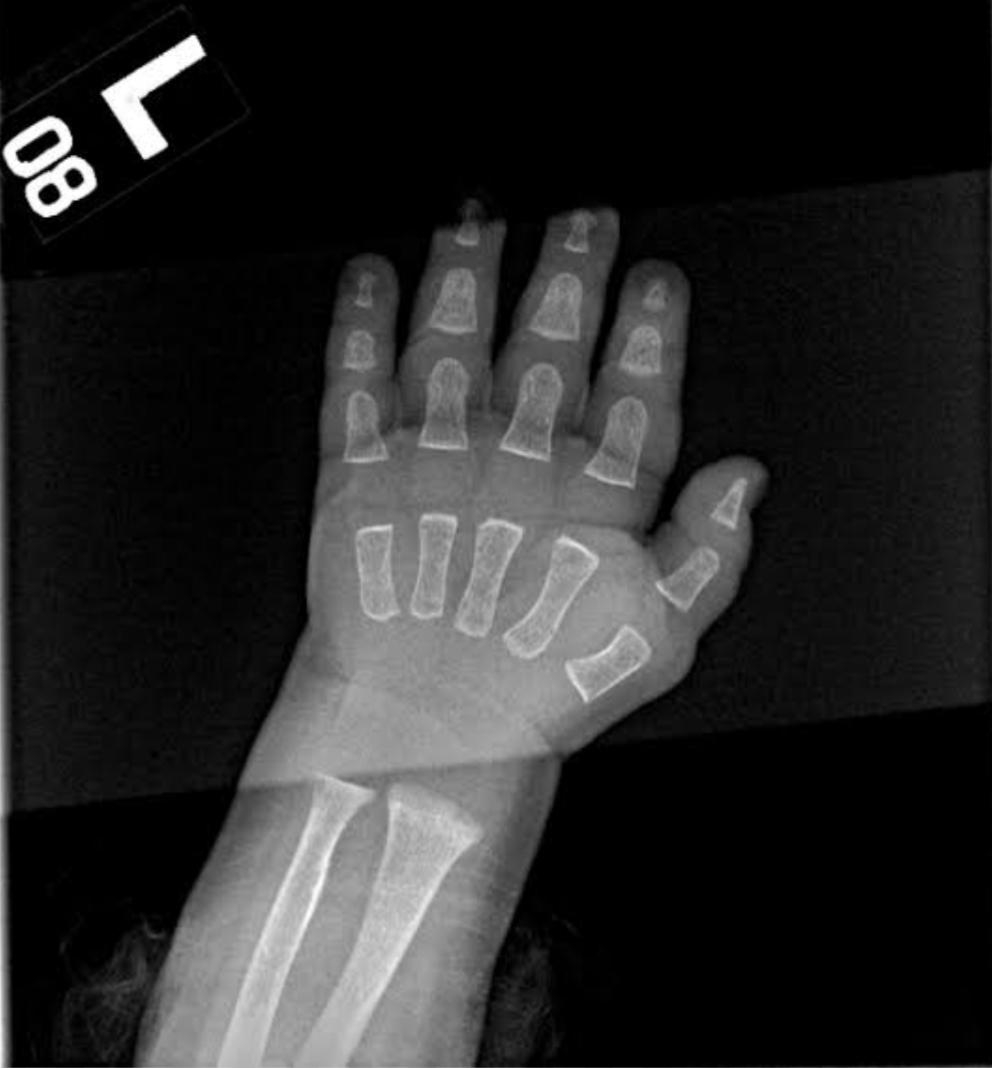

11.This is what an x-ray of a baby’s hand looks like: